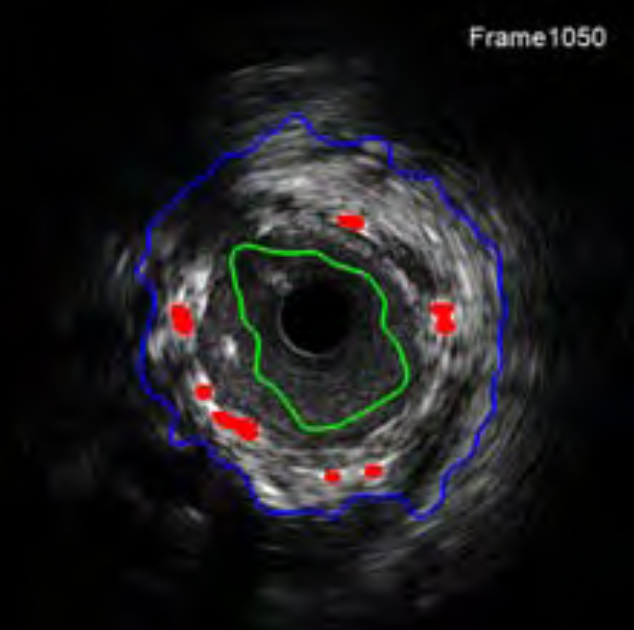

Intravascular ultrasound segmentation

Support vector machines